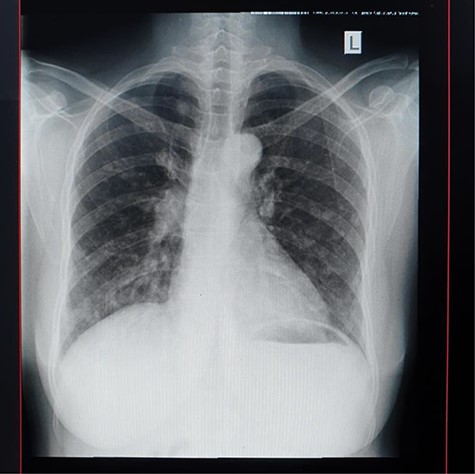

An abdominal ultrasound showed a mass in the posterior wall of the urinary bladder measuring 6 cm × 7 cm with areas of necrosis. There was left moderate ureter hydronephrosis. The right kidney and the rest visceral organs were normal. Chest X-ray revealed multiple macronodules all over the lung fields. Heart size, costophrenic and cardiophrenic angles were all normal (Fig. 6).

The final diagnosis of metastatic adenocarcinoma of the urinary bladder was made and the patient was referred for palliative radiation therapy.